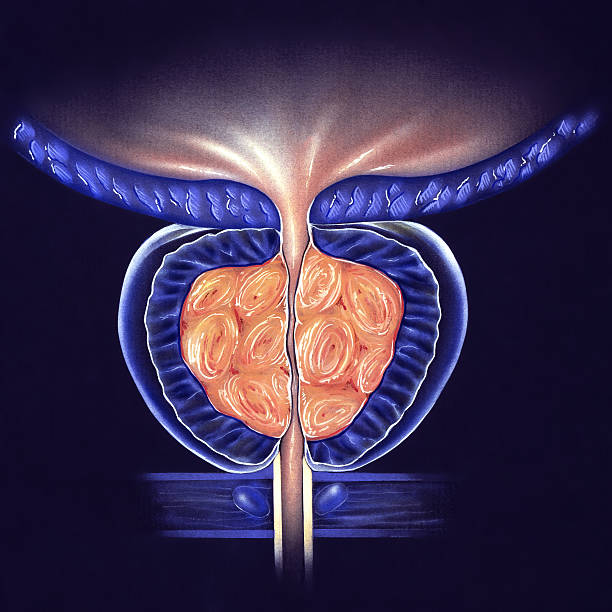

전립선비대증은 남성에서 주로 발생하는 전립선의 비대증입니다. 전립선은 남성의 생식기로서, 요도 주변에 위치하며, 요도를 통해 배뇨와 정액의 배출을 조절합니다. 전립선비대증은 나이가 들수록 발생 확률이 높아지며, 대부분의 남성이 한 번 이상 경험하게 되는 질환입니다.

전립선비대증은 전립선의 세포가 비정상적으로 증식하면서 발생합니다. 이러한 세포 증식으로 인해 전립선이 커지면서 요도 주변을 압박하고, 배뇨와 관련된 증상을 유발합니다. 전립선비대증은 일반적으로 배뇨 불편, 방광염, 자주 병원가는 등의 증상을 유발합니다.